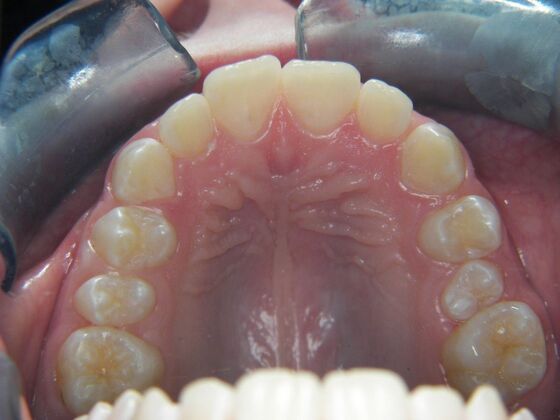

Orthodontics: Case 2

Description

Patient is 9 years old and presents with 100% overbite and blocked out upper and lower lateral incisors. Both upper central incisors are palatally inclined causing a lack of space available for most anterior teeth. Advised her parents that she needs Phase I Interceptive Orthodontic treatment to provide room for all upper and lower front teeth. Phase I treatment was begun and finished, then began Phase II treatment shortly thereafter to finalize case. Removable retainer were fabricated for retention.